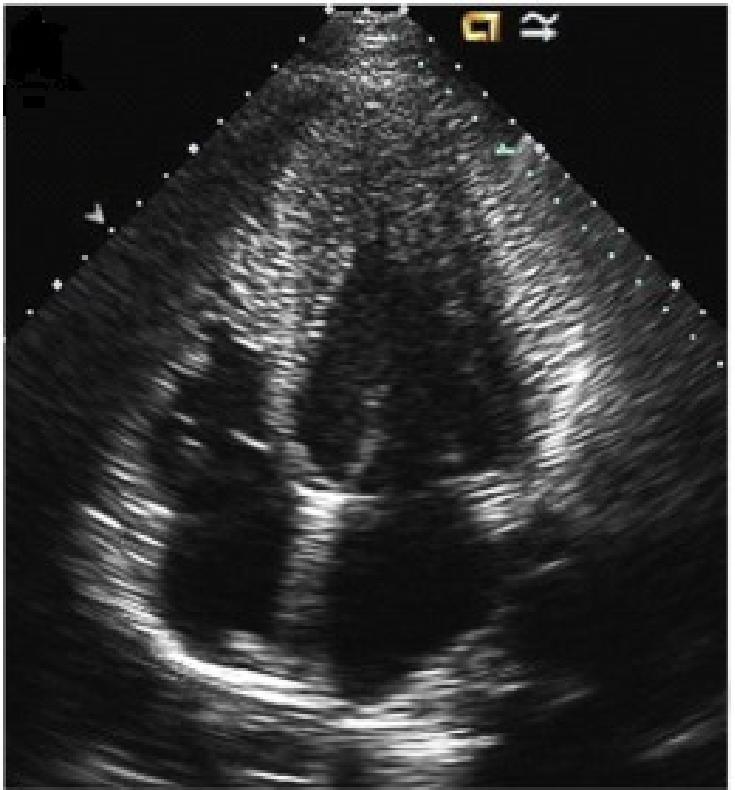

2. 超声心动图:

可检出心肌肥厚的部位及程度,通常肥厚≥15 mm。

超声心动图是确诊本病的有效易行的手段;